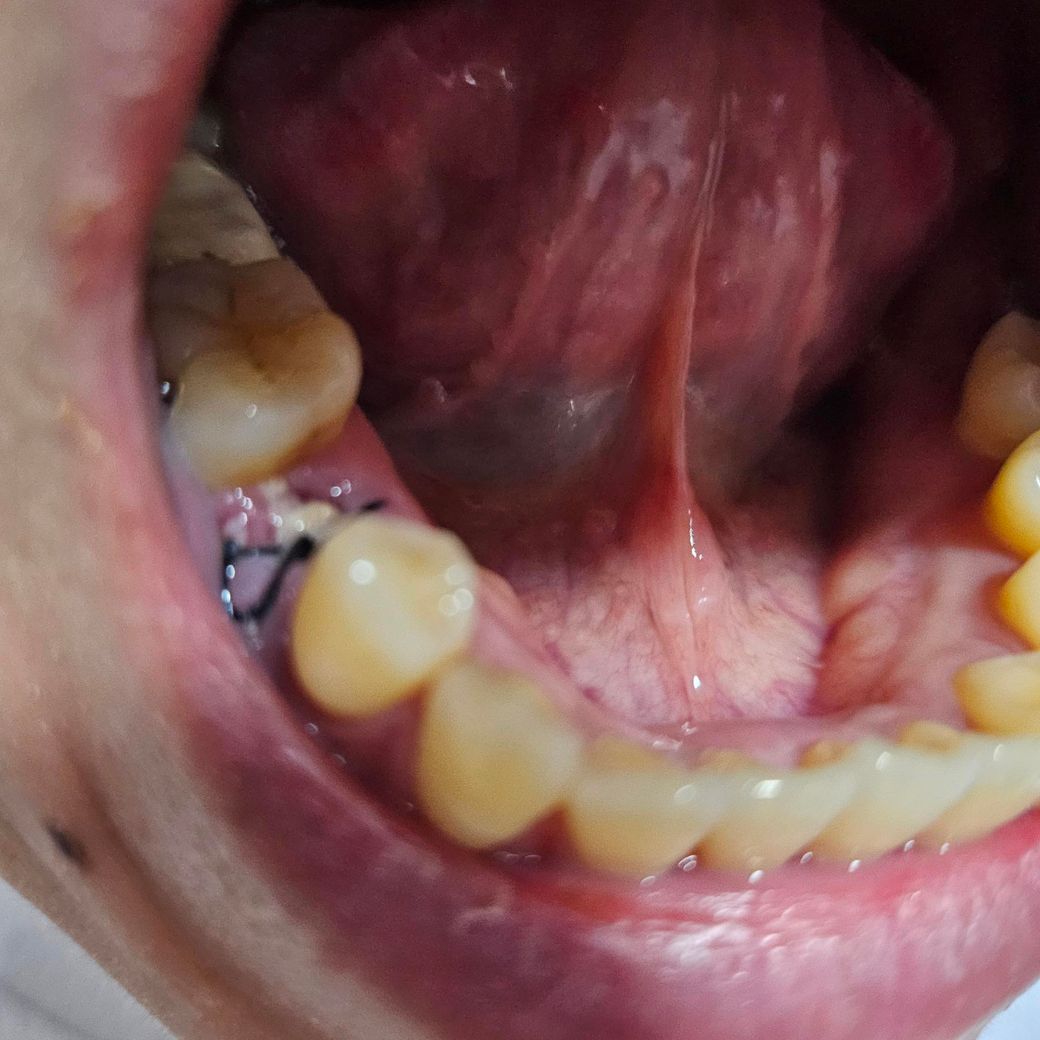

월요일 임플란트발치하고 기둥세우는거처음 했어요

그날만 욱신거리고아무렇지도않아요..

이게괜찮은건가요? 염증난건가.. 잘모르겠어서ㅠㅠ

• 1번 째 사진

사진 상으로는 이물질이 끼어있을 뿐, 염증은 없어보이고 잘 낫고 있는 것으로 판단됩니다.

사진으로 봤을 경우에는 크게 문제가 없이 아물고 있는 것으로 보입니다. 임플란트를 했다면 잇몸에 상처가 있기 때문에 해당 부위가 자극되지 않도록 하는 것이 좋습니다.

사진상으로 보면 발치하고 나서 잇몸이 아물면서 생기는 자연스러운 현상이니 크게 걱정은 안하셔도 될것같습니다.

사진상 수술 부위는 별다른 이상 없습니다. 치과에서 설명해 준 수술 후 주의사항 잘 지키시고, 약 잘 복용하셨으면 됩니다.